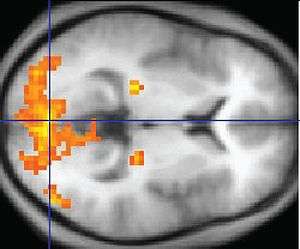

Other methods of obtaining contrast are arterial spin labeling[6] and diffusion MRI. The latter procedure is similar to MRI but uses the change in magnetization between oxygen-rich and oxygen-poor blood as its basic measure. This measure is frequently corrupted by noise from various sources and hence statistical procedures are used to extract the underlying signal. The resulting brain activation can be presented graphically by color-coding the strength of activation across the brain or the specific region studied. [7]